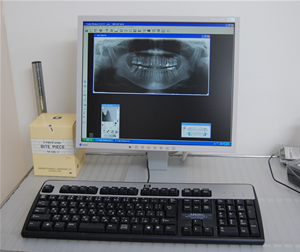

デジタルレントゲン

患者様の健康維持のために旧式のレントゲンの十分の一の線量で撮影が可能で、患者さんをお待たせすることなく撮影画像をすぐお見せすることが出来ます。

また、モニター上で拡大したり濃度を調節したりすることはもちろん、長さを計測することもできますので、より正確な診断が可能になります。